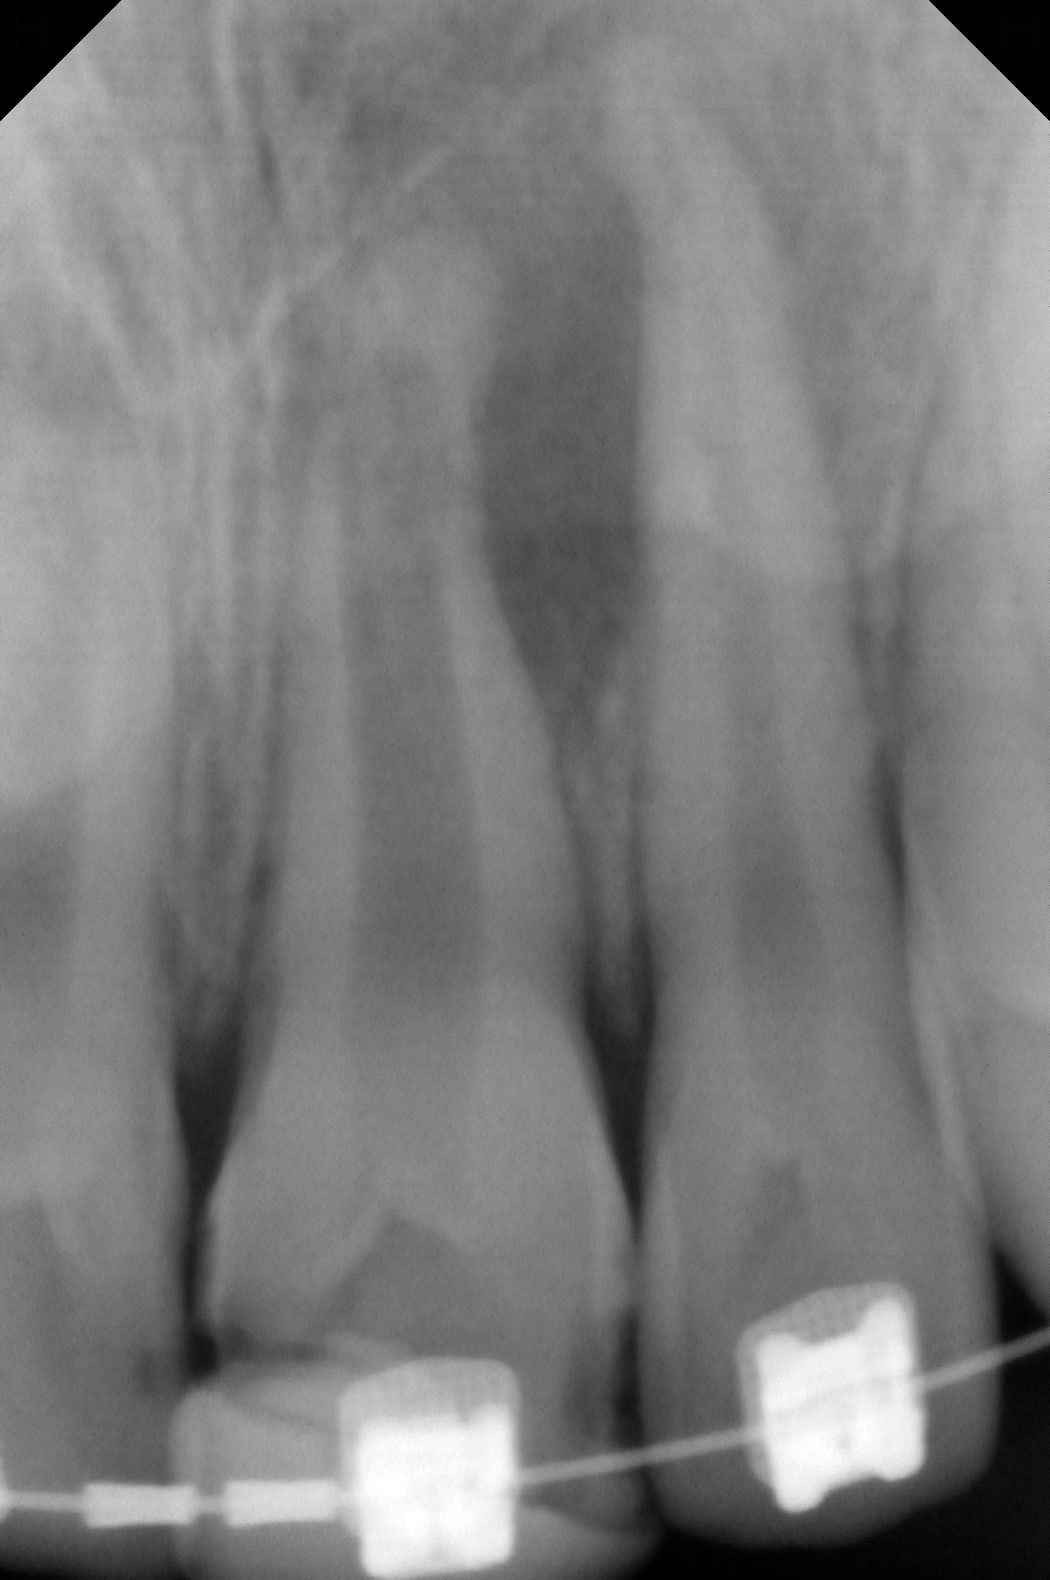

Le premier consulte pour un petit abcès récurrent en regard de la 21 (radio avec lime en place).

Le second consulte parce que son compo sur 21 ne tient plus que parce qu'il est solidarisé à l'arc de son multibague (radio sans la lime).

Voici une 11 d'un patient dont la majorité est passée depuisbien longtemps... et ça tient toujours très bien.

C est très étrange d'avoir une lésion infectieuse à l'apex de ce genre de dents avec apex fermé.

L'apexogénèse ne se termine pas dans les cas de trauma avec nécrose radiculaire. Et de plus il y a souvent des phénomènes de résorption externe le long des racines et aux apex que l'on ne semble pas retrouver ici.

Si c'est bien fermé il n'y a aucune difficulté dans tes traitements tu fais une endo classique sans aucun risque de dépassement. Il vaut mieux obturer avec de la biocéramique car plus de solidité pour la dent.

Mais attention si apex totalement fermé et pas de perméabilité apicale, peu de chance d'avoir une cicatrisation de tes lésions.